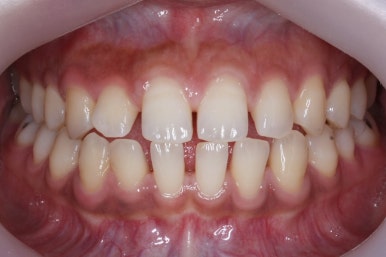

위 사진은 부산치아교정치과에 내원하셨을 대 당시의 입안 모습입니다.

치아들 사이에 전반적으로 틈이 많이 있는 상태입니다.